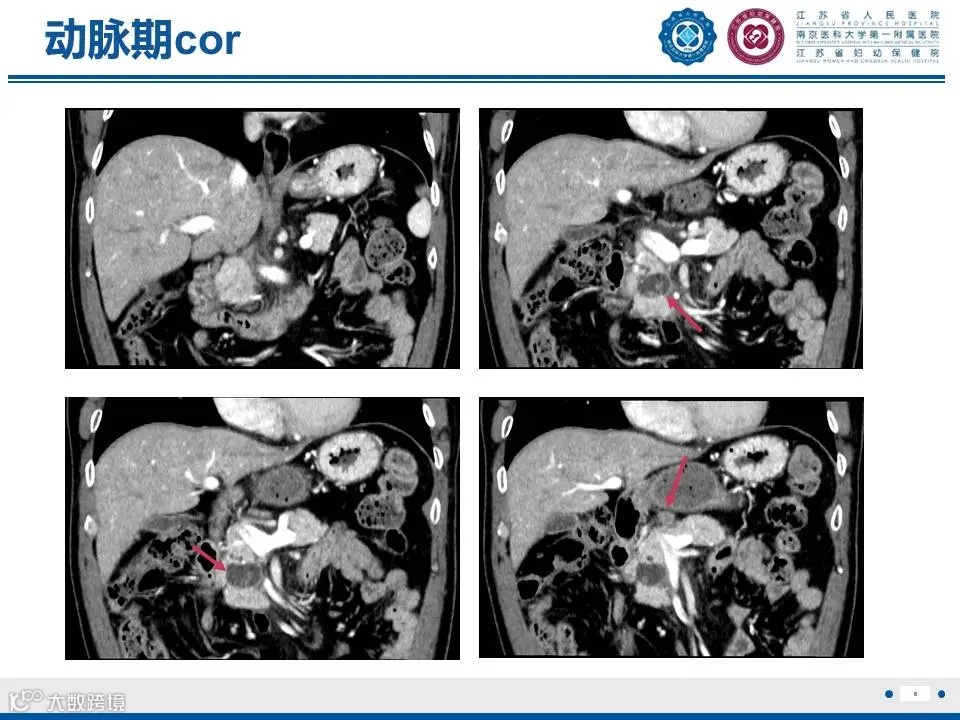

来源:江苏省人民医院放射科